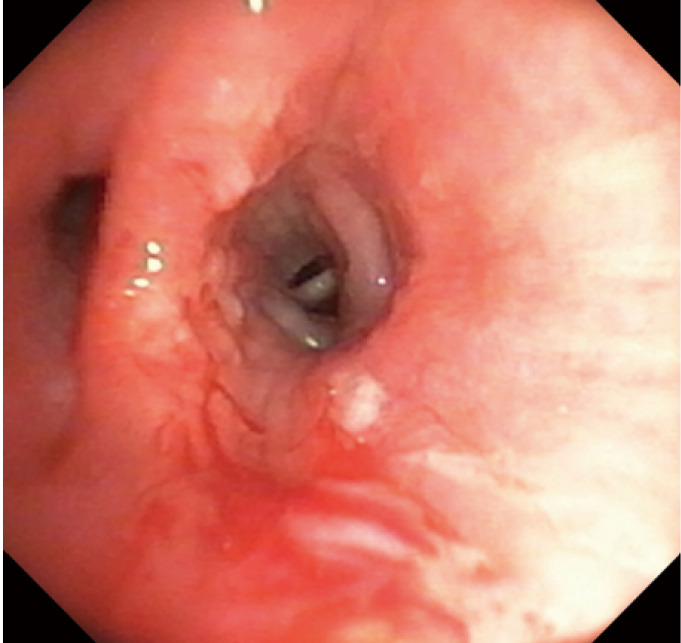

Figure 6.

Rat tooth forceps being used for the retrieval of airway foreign body in a simulation session.